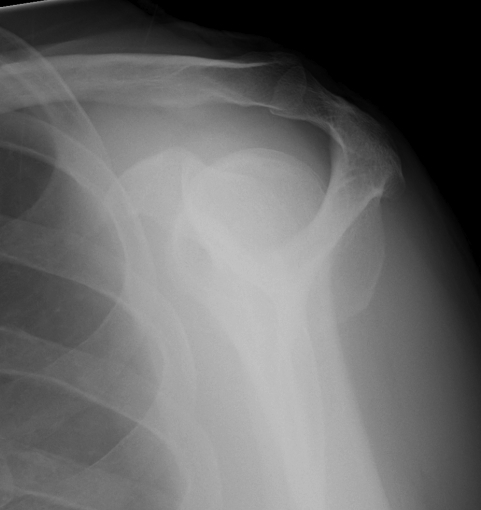

AP IR / ER

Demonstrates Hill Sach's and other humeral head morphology